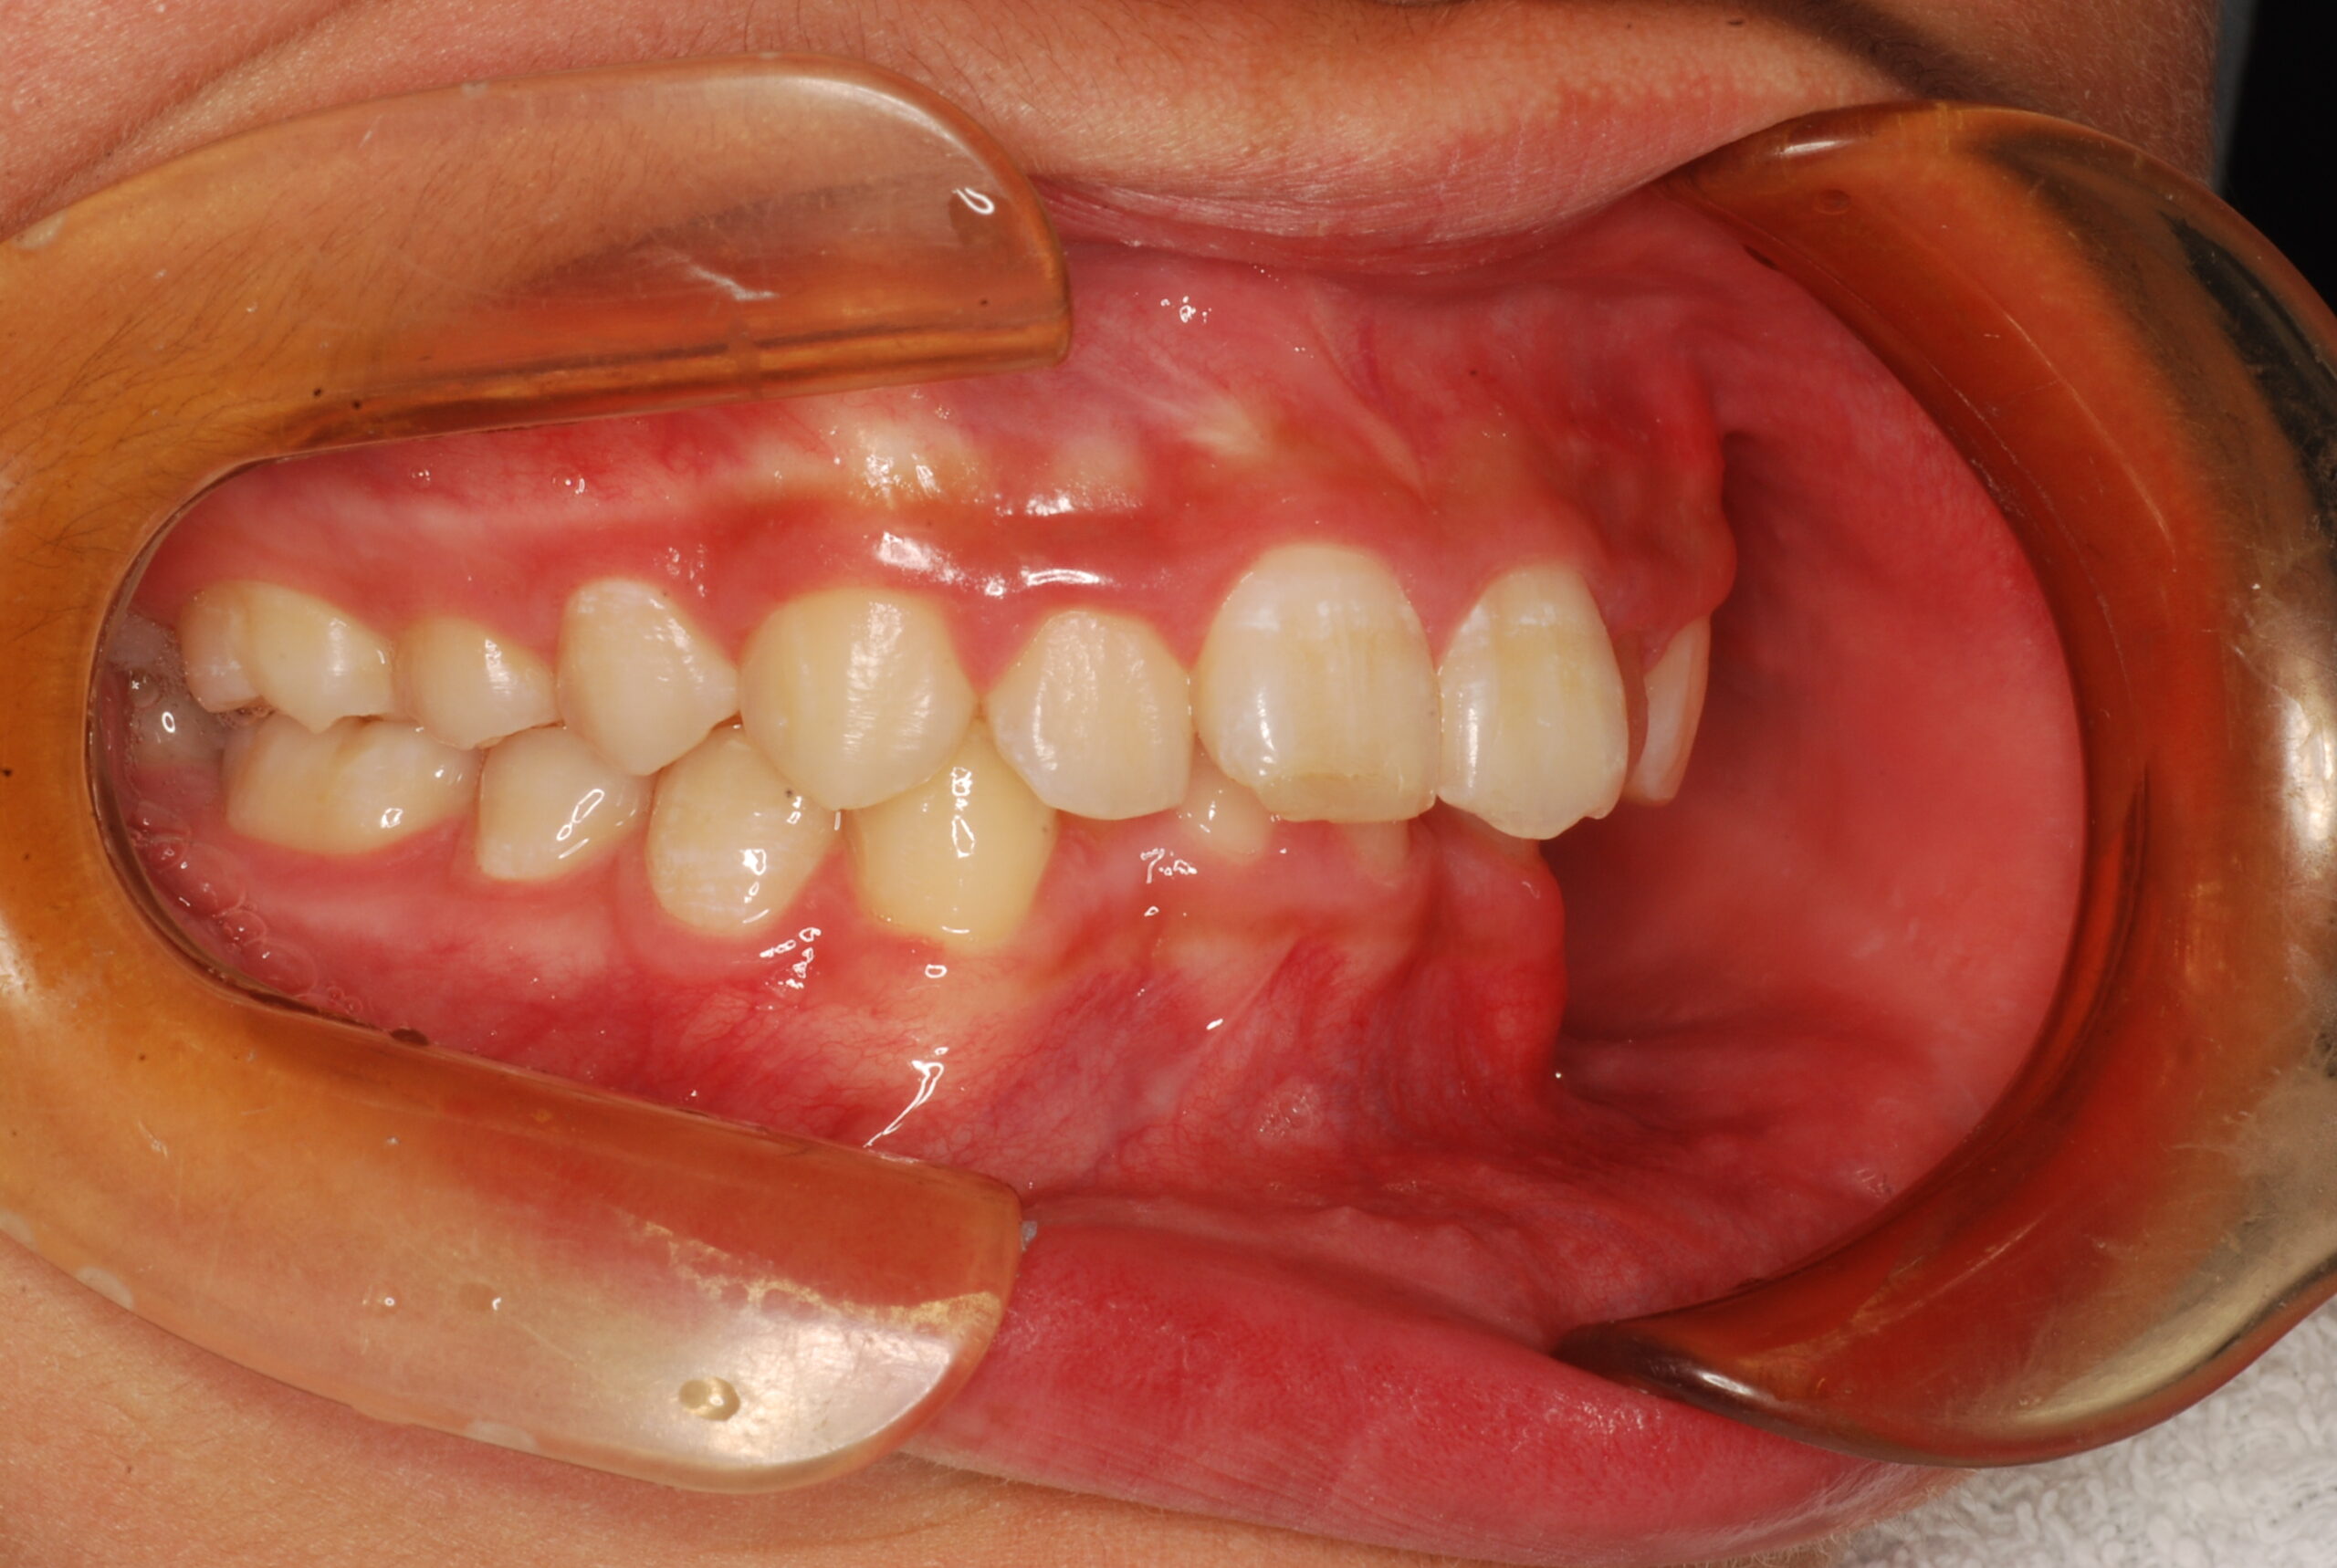

過蓋咬合・叢生 13歳男性

13歳9ヶ月 男性

治療後

【診断】叢生、過蓋咬合

【治療方法】上下両側第一小臼歯抜歯、ワイヤー治療期間3年間、上顎口蓋にTPA(トランスパラタルアーチ)を行いました。